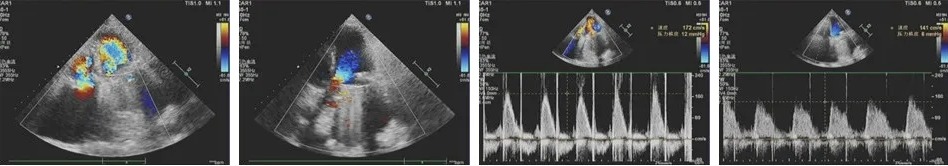

患者术后一个月复查心脏超声

1、二尖瓣位机械瓣置换术后,二尖瓣位机械瓣功能良好。

2、 三尖瓣位生物瓣置换术后,生物瓣功能良好。

3、心功能:左室整体收缩功能尚好(LVEF:59.0%)。右室整体收缩功能尚好(RV FAC:39%)。